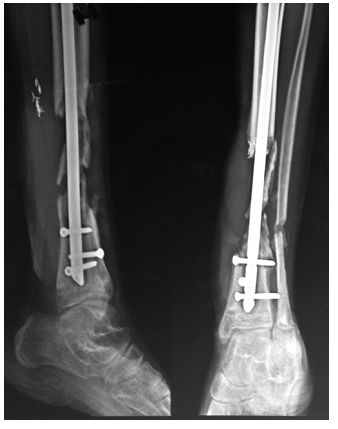

胫骨骨不连临床并不少见,下图为以19岁男性,髓内钉固定后发生感染性骨不连。

➤ 1、I期取掉内固定物;

➤ 2、彻底清创;

➤ 3、采用带抗生素的骨水泥做成的spacer(间隔块),比如下图里用3根克氏针+骨水泥做成的间隔块;

➤ 4、并用外固定支架支撑。